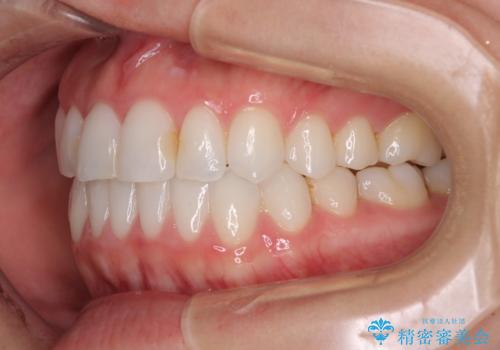

前歯のクロスバイトを治したい インビザラインによる矯正治療

- 前歯のデコボコとクロスバイトを治したいとのことで来院された患者様です。

上下顎ともに歯列全体の側方拡大とIPR(歯と歯の間を削る)によってデコボコとクロスバイトが解消するように設計し、インビザラインにより治療を行うこととしました。

下顎骨の左側への骨格的なずれが強く、上下の正中の位置合わせや奥歯の咬み合わせ構築に苦労しました。